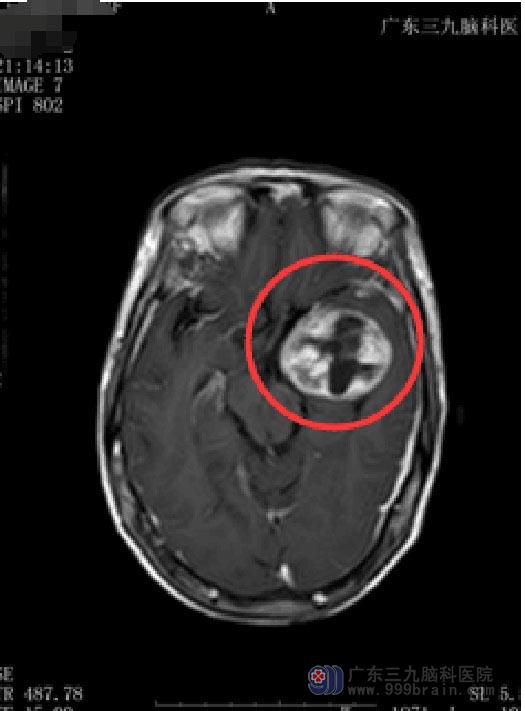

10天前开始出现阵发性头晕;两天因头晕摔倒致“右锁骨骨折”。当地医院检查示肿瘤较前增大,广东三九脑科医院MR显示:1.左侧鞍旁占位性病变,大小约4.5cm×3.9cm×4.5cm,考虑神经鞘瘤可能,待排骨源性肿瘤。

由于占位巨大,通过传统的单一开颅或经鼻蝶入路手术不可能全切肿瘤,若是采取分期手术,则将会大大增加患者再次手术风险以及住院费用。经过充分的术前讨论、评估后,鲁明副院长决定为其实施“内镜经鼻蝶+左侧翼点联合入路颞下窝巨大占位切除术”。导航定位,确定肿瘤位置,显微镜下分块全切肿瘤,术中视神经、动眼神经、颈内动脉及其分支血管保护完好,术后患者恢复良好,视力、视野较前好转,无脑脊液漏发生,无尿崩及电解质紊乱。术后病理:(左侧鞍旁)神经鞘瘤。